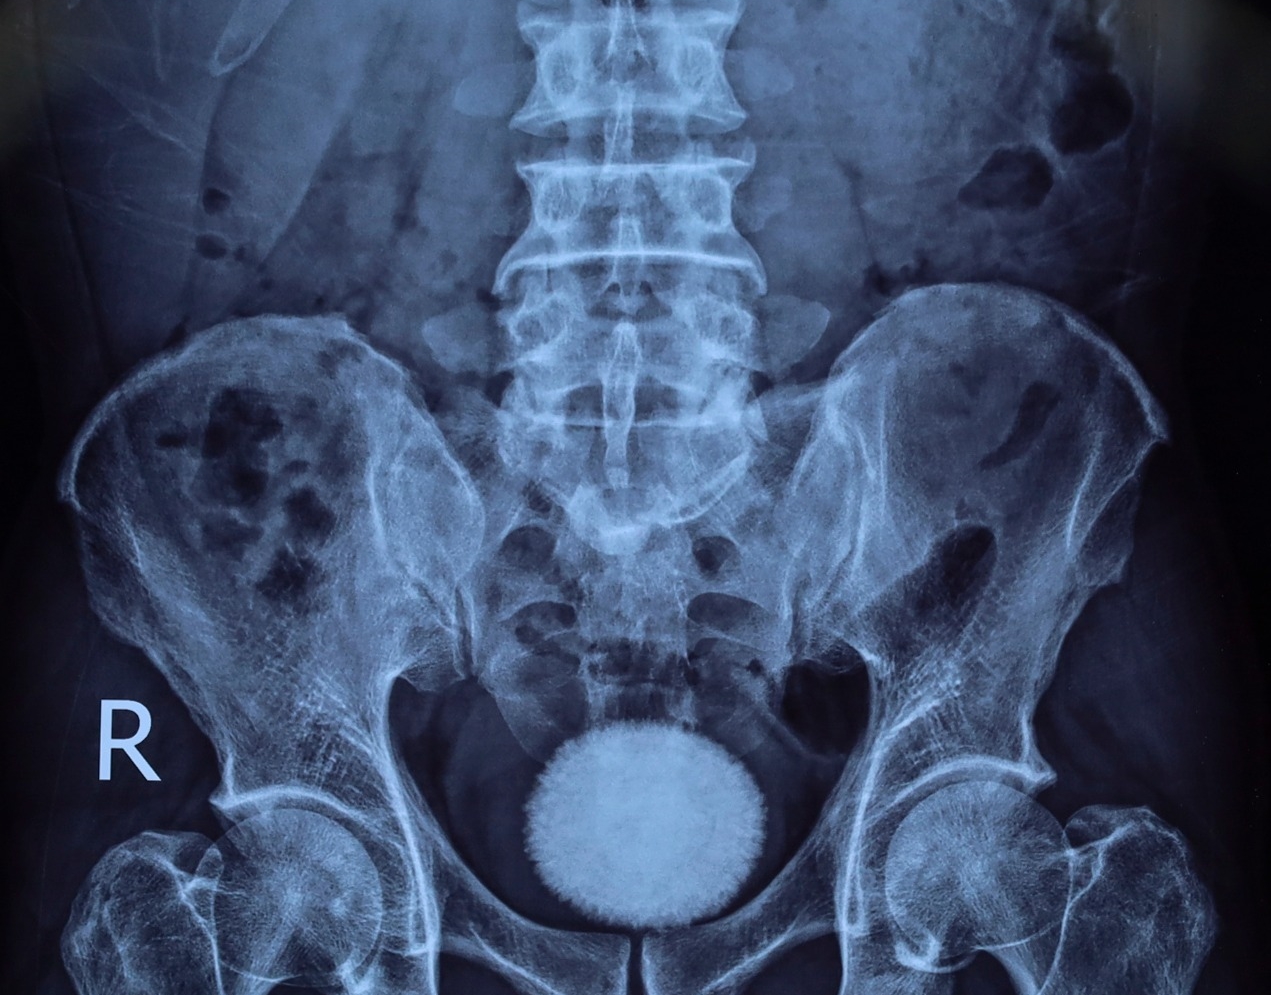

Trước đó, bệnh nhân đến khám trong tình trạng tiểu buốt, tiểu khó kéo dài, kèm đau vùng hạ vị. Qua thăm khám lâm sàng, siêu âm và chụp X-quang, các bác sĩ phát hiện trong bàng quang có viên sỏi kích thước khoảng 60×40 mm.

Nhận định đây là viên sỏi lớn, nguy cơ gây tắc nghẽn và nhiễm trùng đường tiết niệu, ê kíp bác sĩ đã chỉ định phẫu thuật mở lấy sỏi bàng quang.

Viên sỏi bàng quang kích thước khoảng 60×40 mm được lấy ra sau phẫu thuật tại Bệnh viện Ngoại khoa 115 Nghệ An.

Trong quá trình phẫu thuật, các bác sĩ rạch da đường giữa trên xương mu, tiếp cận bàng quang và lấy ra một viên sỏi lớn, kích thước tương đương quả trứng ngỗng. Sau khi lấy sỏi, bàng quang được bơm rửa sạch và khâu phục hồi theo đúng quy trình chuyên môn. Ca mổ diễn ra thuận lợi. Hiện bệnh nhân tỉnh táo, sức khỏe ổn định và đang được theo dõi, chăm sóc hậu phẫu.